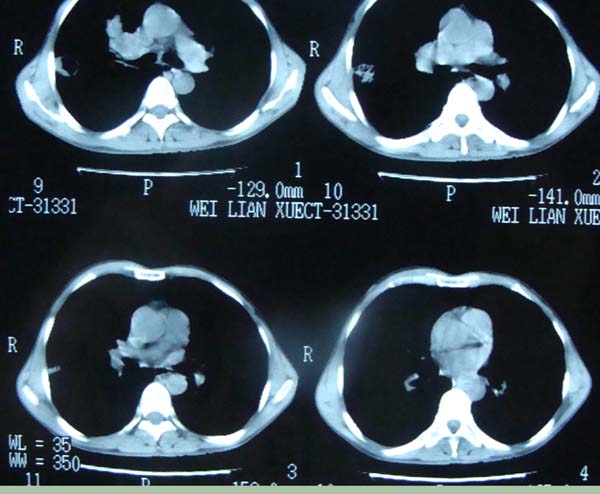

以下是引用pujunzhi在2009-6-21 21:48:00的发言:[br]右肺上叶后段见一空洞性病灶,灶周有渗出即晕征,右肺门肿大---可考虑感染性空洞和癌性空洞,先抗炎抗痨后复查并完善相关检查。有癌性空洞伴肺门淋巴结转移的可能。